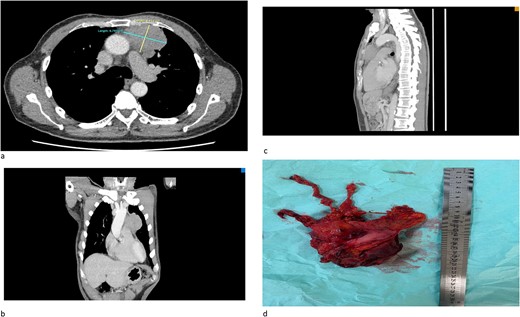

(a) An axial cut of a contrast-enhanced computed tomography (CECT) scan thorax showing an ill-defined anterior mediastinal mass measuring 4.8 cm × 6.7 cm. (b) A coronal view of a CT scan showing an ill-defined anterior mediastinal mass infiltrating the left upper and middle lobe lung. (c) A sagittal view of a CT scan showing an ill-defined anterior mediastinal mass. (d) A successful total thymectomy with R0 resection (microscopically margin-free resection) through a primary median sternotomy.

We would like to report a case of a 67-year-old male with no known co-morbidity who initially presented with generalized fatigue and hemoptysis. The serial bloods results are consistent with persistent hyponatremia. The patient was diagnosed with a duodenal ulcer after orogastroduodenoscopy and SIADH in view of persistent hyponatremia. Initial chest X-ray showed incidental findings of a widened mediastinum, and computed tomography (CT) scan of the thorax confirmed the presence of anterior mediastinal mass (Fig. 1a-c). CT-guided biopsy was inconclusive of the diagnosis and hence referred for surgical intervention. Serum osmolarity, urine osmolarity, and urine sodium were normal despite being followed up with SIADH. CT brain showed no evidence of intracranial involvement.

The patient successfully underwent total thymectomy with pericardium, lower part of upper lobe, and upper part of the lower lobe of the left lung en bloc resection (Fig. 1d). The patient was discharged well. The histopathology (HPE) specimens were reported as poorly differentiated cancer with lung invasion (T3N1MX). He was then referred to the oncology team, and successfully completed four cycles of adjuvant chemotherapy using the ‘paclitaxel carboplatin regime’. His follow-up investigations showed complete resolution of hyponatremia and his symptoms revolved after completion of chemotherapy.